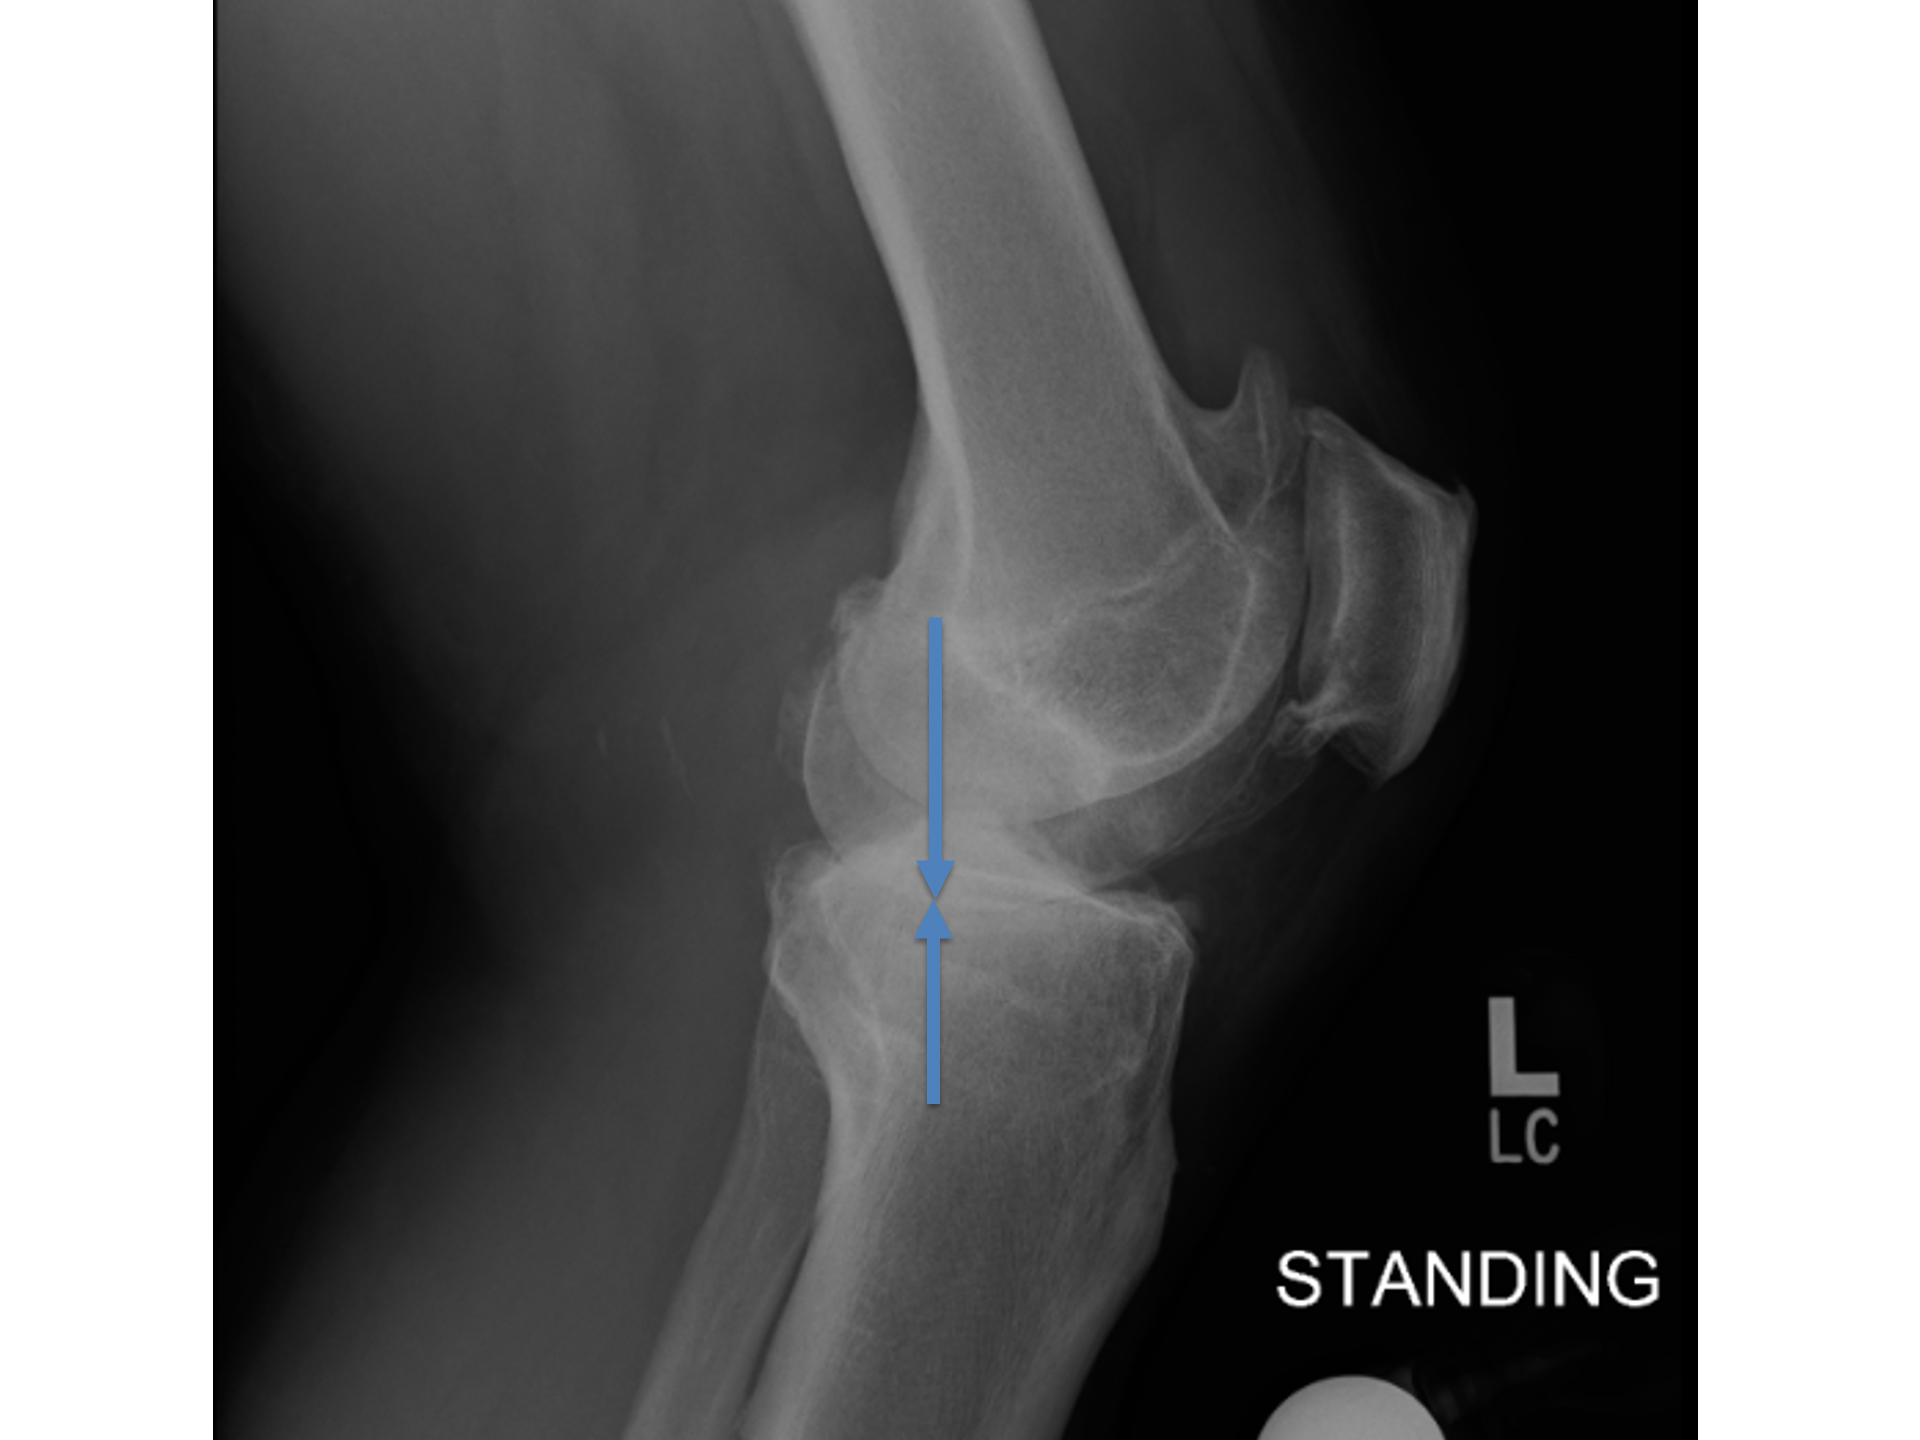

Importantly..

The cartilage loss has spared the back of the knee.

That tells us that the anterior cruciate ligament (ACL) is intact.

The ACL is the ligament that footballers sometime injure or rupture

It gives the knee front to back stability

And stops the tibia coming forward.

So, if the cartilage at the back of the knee is intact

There must be an..

Intact ACL